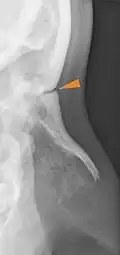

Frontonasal suture

The frontonasal suture (Latin: Sutura frontonasalis) is a cranial suture that is found in the human skull, connecting the frontal bone and the two nasal bones.[1] This suture meets the internasal suture at the nasion. It is crucial in the study of cranial development and forensic analysis.